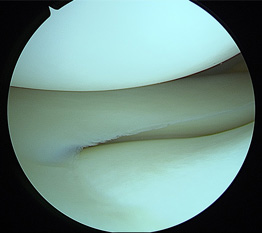

• 画像:損傷後外側半月板関節鏡画像

損傷後外側半月板関節鏡画像